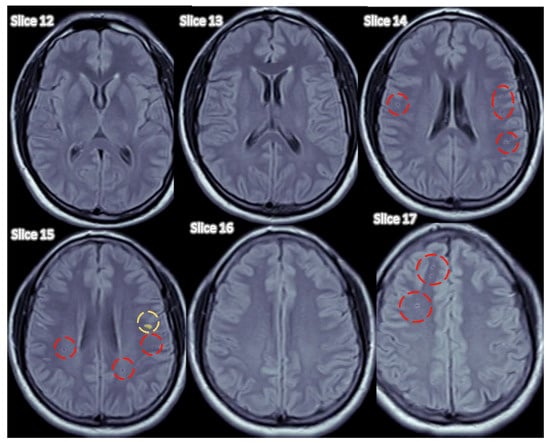

4.2.4. Detectron2 for Detecting WMH Lesions